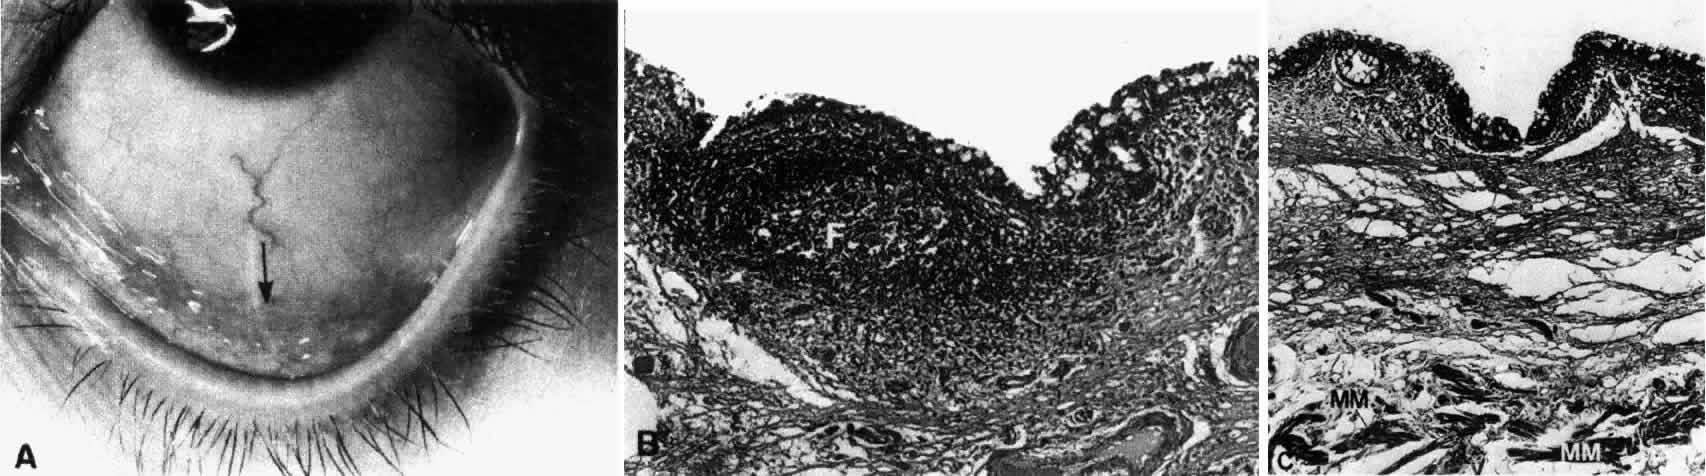

Fig. 1. Low-power view of the globe. A. Arrow pointing to the region of the superior fornix. B. Superior fornix (F) showing epithelium and substantia propria. Conjunctival sac (CS). C. Higher-power view of epithelium showing goblet cells on the surface (arrows). (B, × 50; C, × 170)

Fig. 2. A. Region of the inferior fornix (arrow). B. Inferior fornix showing epithelium, goblet cells, and a follicle (F). C. Inferior fornix showing Müller's muscle (MM) in the substantia propria. (B, × 60; C, × 80)

The conjunctiva lines the posterior surface of the upper and lower lids and the anterior surface of the globe. From the inner surface of the lid it is reflected forward onto the globe above and below, forming two recesses: the superior and inferior fornix. The superior fornix is located at the level of the orbital margin 8 to 10 mm from the limbus (Fig. 1A, B, and C). The inferior fornix is approximately 8 mm from the limbus (Fig. 2A, B, and C). On the medial side, the forniceal structures are replaced by the caruncle and the plica semilunaris (Fig. 3). The absence of the fornix on the medial side is necessary in order to allow the inferior punctum to dip and drain from the superficial tear fluid layer.10 Laterally, the fornix extends just behind the equator of the globe (Fig. 4). It is quite deep and approximately 14 mm from the limbus.